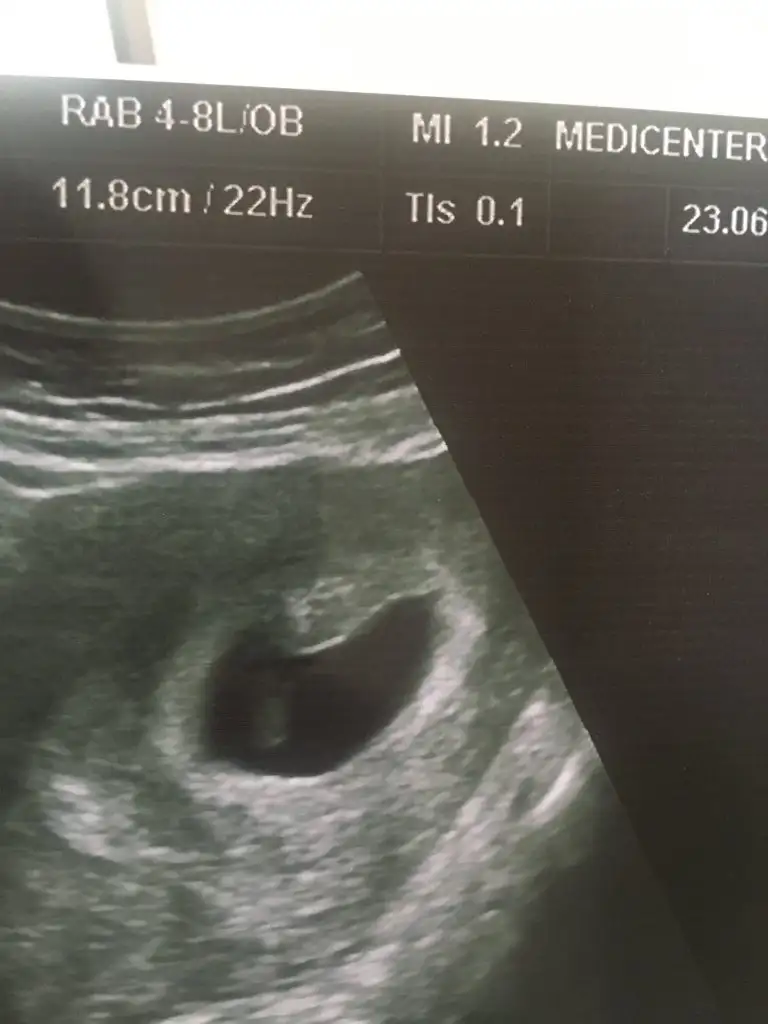

Yaa yorumunuzu gördüm şimdi benimki de sağ üstte mi oluyor bakar mısınız erkek mi :) karından usg

Eklentiler

• 019B0AF0-58BE-4719-B938-232FC0DF606F.webp

37,1 KB · Görüntüleme: 803